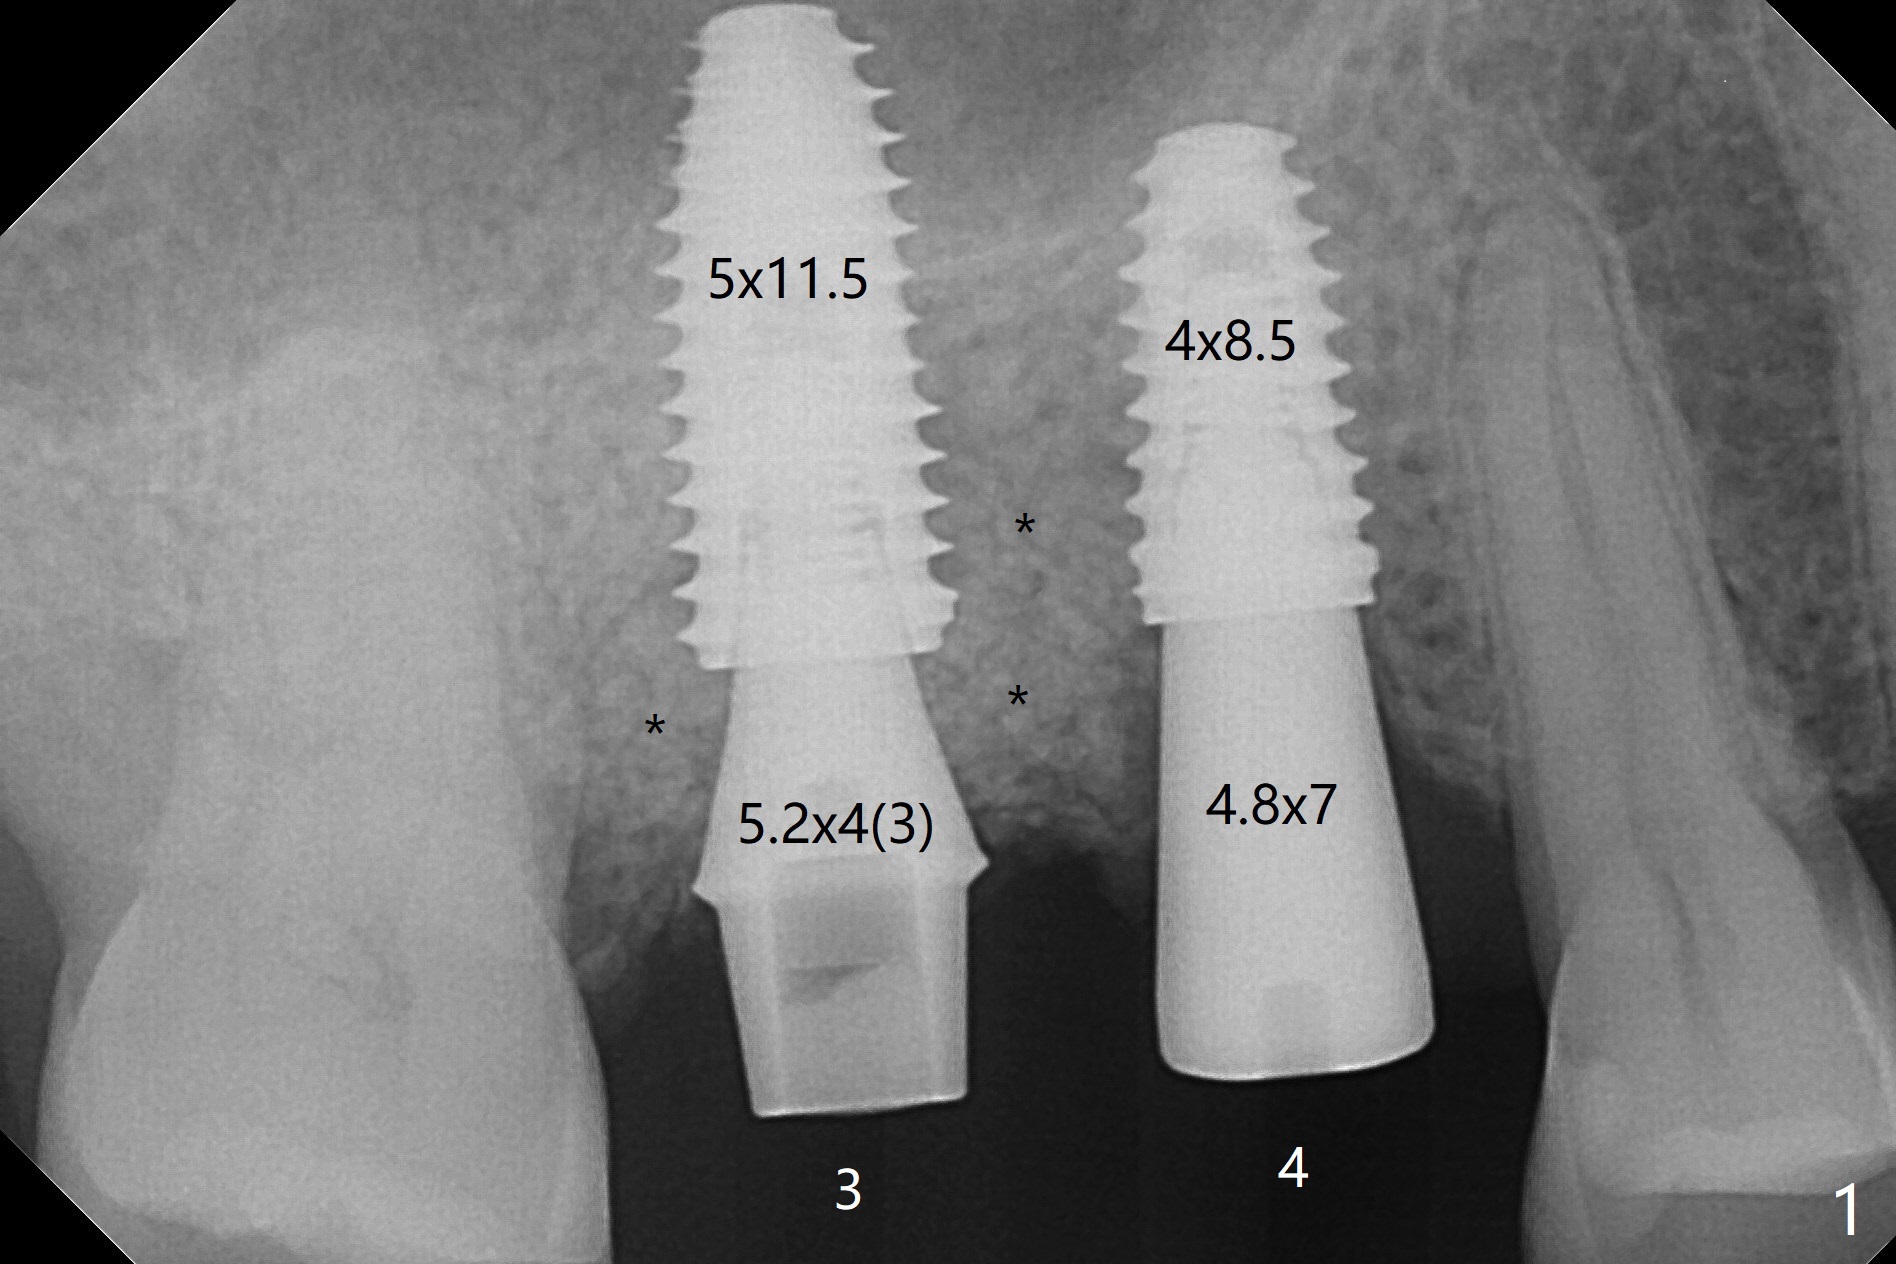

When the tooth #3 with severe buccal gingival recession is extracted and implants are placed at #3 and 4 with guide, sticky bone in 2 large pieces is packed between these implants with a previously large defect in a seemingly secure manner (Fig.1 *). Use of a longer implant at #3 (11.5 mm vs. 10 mm) will reduce the chance of abutment screw loosening in the future. With 2 pieces of PRF membrane coverage, an immediate provisional is fabricated for graft retention (Fig.2,3 P). To stabilize a buccal flap (Fig.2 *, used to be buccal furca gingiva), periodontal dressing is applied later. The buccal socket heals 12 days postop (Fig.4). Apparently new bone forms between the implants 4 months postop (Fig.5). The abutment at #3 may not be completely seated. In fact it is loose, probably related to buccal gingival and gingival cuff erythema 6.5 months postop (Fig.6). Large healing abutments are placed to form the interdental (interimplant) papilla without effect (*). Provisional crowns will be fabricated for the papilla formation. When cemented abutments are placed (Fig.7), papilla formation by manipulation of provisional crowns seems unlikely. Impression is taken. Although there is no implant thread exposure, the buccal plate is concave 7.5 months postop (Fig.8). With special crown design, food impaction should be minimal post cementation (Fig.9,10). There is no bone loss 5.5 months post cementation (Fig.11), while the soft tissue is healthy (data not shown).